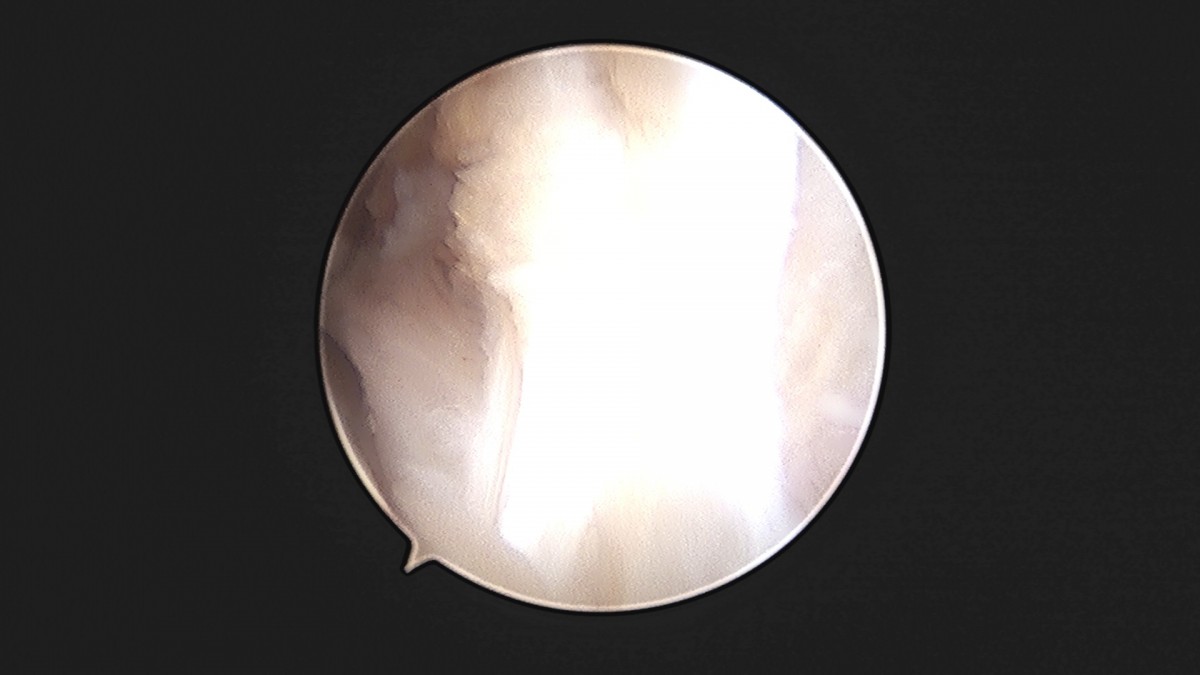

이재상원장님 발목 인대 봉합술 이주O 환자

dae765e4d9ac96aee867c9d6292d8784_1758007208_3244.jpg